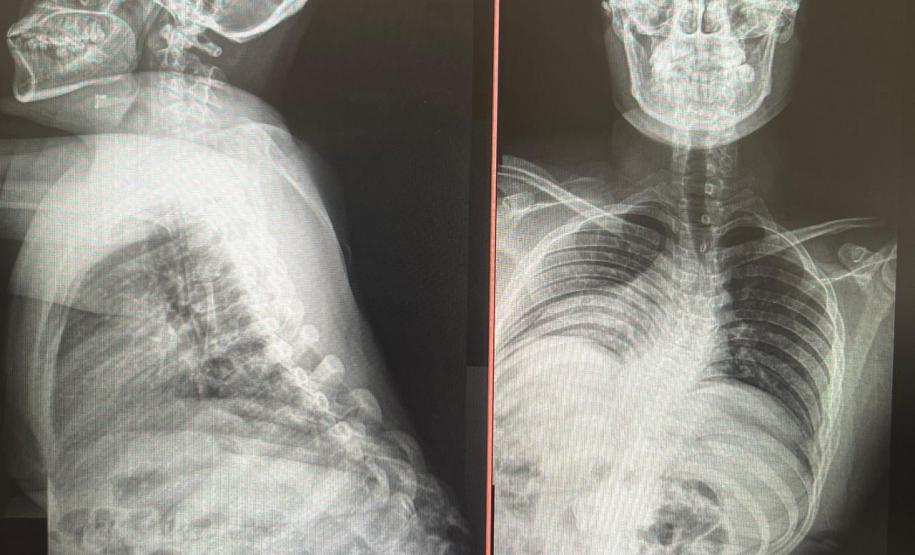

Outro tipo de escoliose é a causada por doenças neuromusculares, como paralisia cerebral, mielomeningocele, distrofia muscular, atrofia muscular espinhal, entre outras. No caso do Lucas Batista da Paixão, de 18 anos, a paralisia cerebral que teve ao nascer foi o que desencadeou a condição.

Com curvatura acima dos 100 graus, desconfortos respiratórios como falta de ar e asma, a posição do adolescente na cadeira de rodas estava bem limitada. Para a mãe de Lucas, Daniele de Oliveira Batista, a cirurgia foi fundamental para melhorar a autonomia e qualidade de vida do filho.

“Foi um longo processo até chegar aqui no CHT, esperávamos por essa cirurgia há mais de dois anos e, depois de tantas dificuldades, hoje conseguimos fazer um passeio sem que ele reclame de dor. Ele também já consegue ficar em muitas outras posições que antes eram desconfortáveis e geravam muita dor. Só temos a agradecer a toda equipe médica pelos cuidados e ótimo atendimento prestado ao meu filho”, disse.